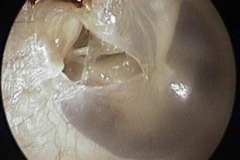

Perforation